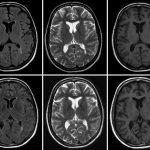

Причины хронической ишемии головного мозга К главным причинам хронической ишемии головного мозга относят артериальную